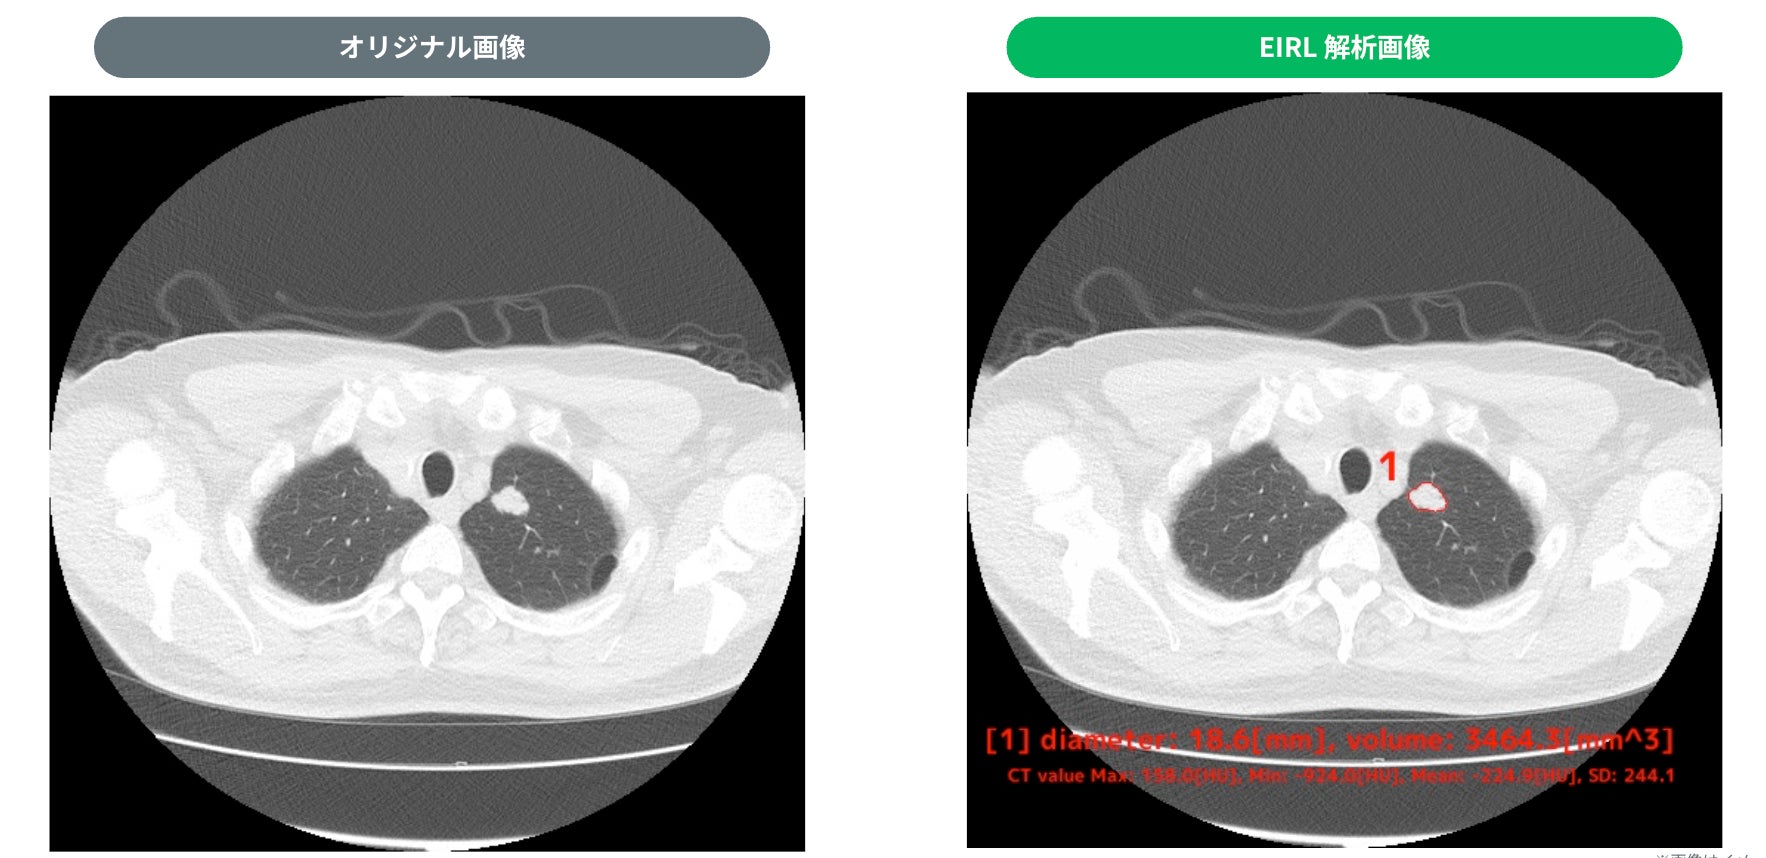

・検出例

① 18.6mm 充実型